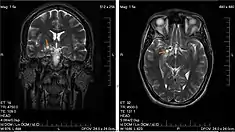

Glioma in the left parietal lobe (brain CT scan), WHO grade 2 | |